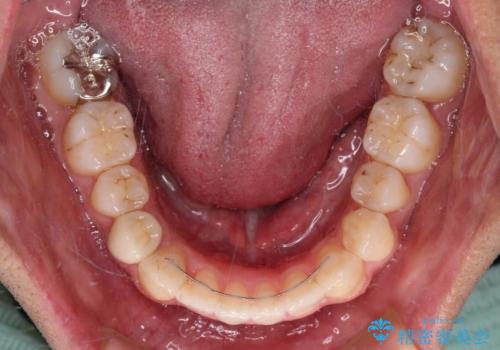

奥歯の咬み合わせは接触が少なく物足りないように見えますが、患者様としては十分に咬むことができるとのことでした。

- 前歯のデコボコとクロスバイトを気にして来院された患者様です。

下顎の歯列弓に対して上顎歯列弓がやや小さく、側方の歯を中心にクロスバイトが見受けられました。

後方に隠れていた上顎前歯は矮小歯であるため、矯正治療の途中でオールセラミッククラウンを装着し、左右対称の大きさでの仕上がりを目指すこととしました。